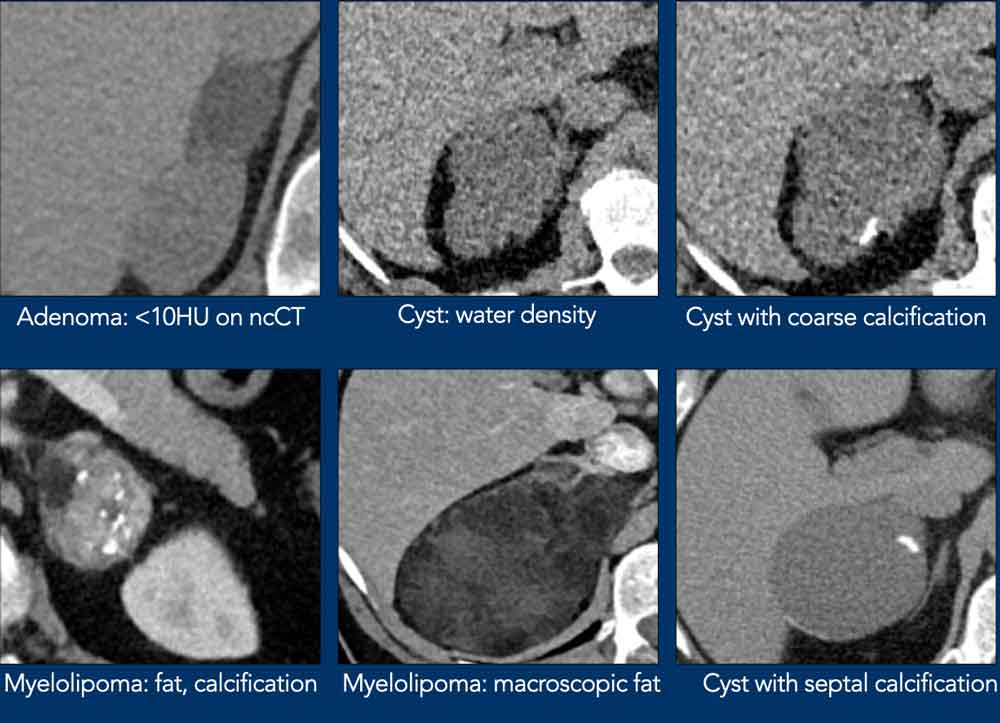

Typically Benign lesions

Many adrenal lesions can be categorized as typically benign and need no follow up (table):

Here some examples of typically benign lesions.

Lipid-rich adenoma

70% of adenomas contain high intracellular fat and will be of low attenuation on unenhanced CT [4,5].

A density equal to or below 10 HU is considered diagnostic of a lipid-rich adenomas.

Using a safe threshold value of 10HU on a native CT scan results in a sensitivity of 70-79% and a high specificity of 96-98% for the diagnosis of an adenoma [5-7].

Cyst

An uncomplicated cyst is a well-defined lesion of water density that does not enhance.

A cyst has a thin wall and may have thin septa.

It may be an endothelial cyst or a pseudocyst, which are the most common, or a true epithelial or parasitic cyst (both rare) [5].

Pseudocysts may have thicker walls.

Hemorrhage or debris may cause increased internal attenuation.

Both benign and malignant tumors may show cystic degeneration and necrosis.

In those cases density measurements are unreliable.

Features of an underlying tumor may be an irregular thick wall of 5 mm or more and mural, septal or solid enhancement [5].

Lesions with benign calcifications Lesions with benign calcifications

Lesions with benign calcifications

Coarse rounded, peripheral or septal calcifications are typically benign and may be seen in:

• Adenoma

• Myelolipoma

• Trauma

• Granulomatous infection

Bilateral calcifications also suggest a benign origin.

Punctate, dystrophic and irregular calcifiations are not typically benign and can be seen in:

• Adrenocortical cancer

• Adrenal metastases

Myelolipoma

Myelolipomas are benign tumors composed of bone marrow elements.

Usually they are easy to recognize on CT or MR because they contain areas of macroscopic fat.

Calcifications are seen in 24% of cases.

The adrenal mass seen here on CT contains macroscopic fat, which is specific for the diagnosis myelolipoma.

On the right a different case with high SI on T1W-image indicating macroscopic fat in a myelolipoma.

CT image of another adrenal mass mainly composed of macroscopic fat.

Diagnosis: myelolipoma.